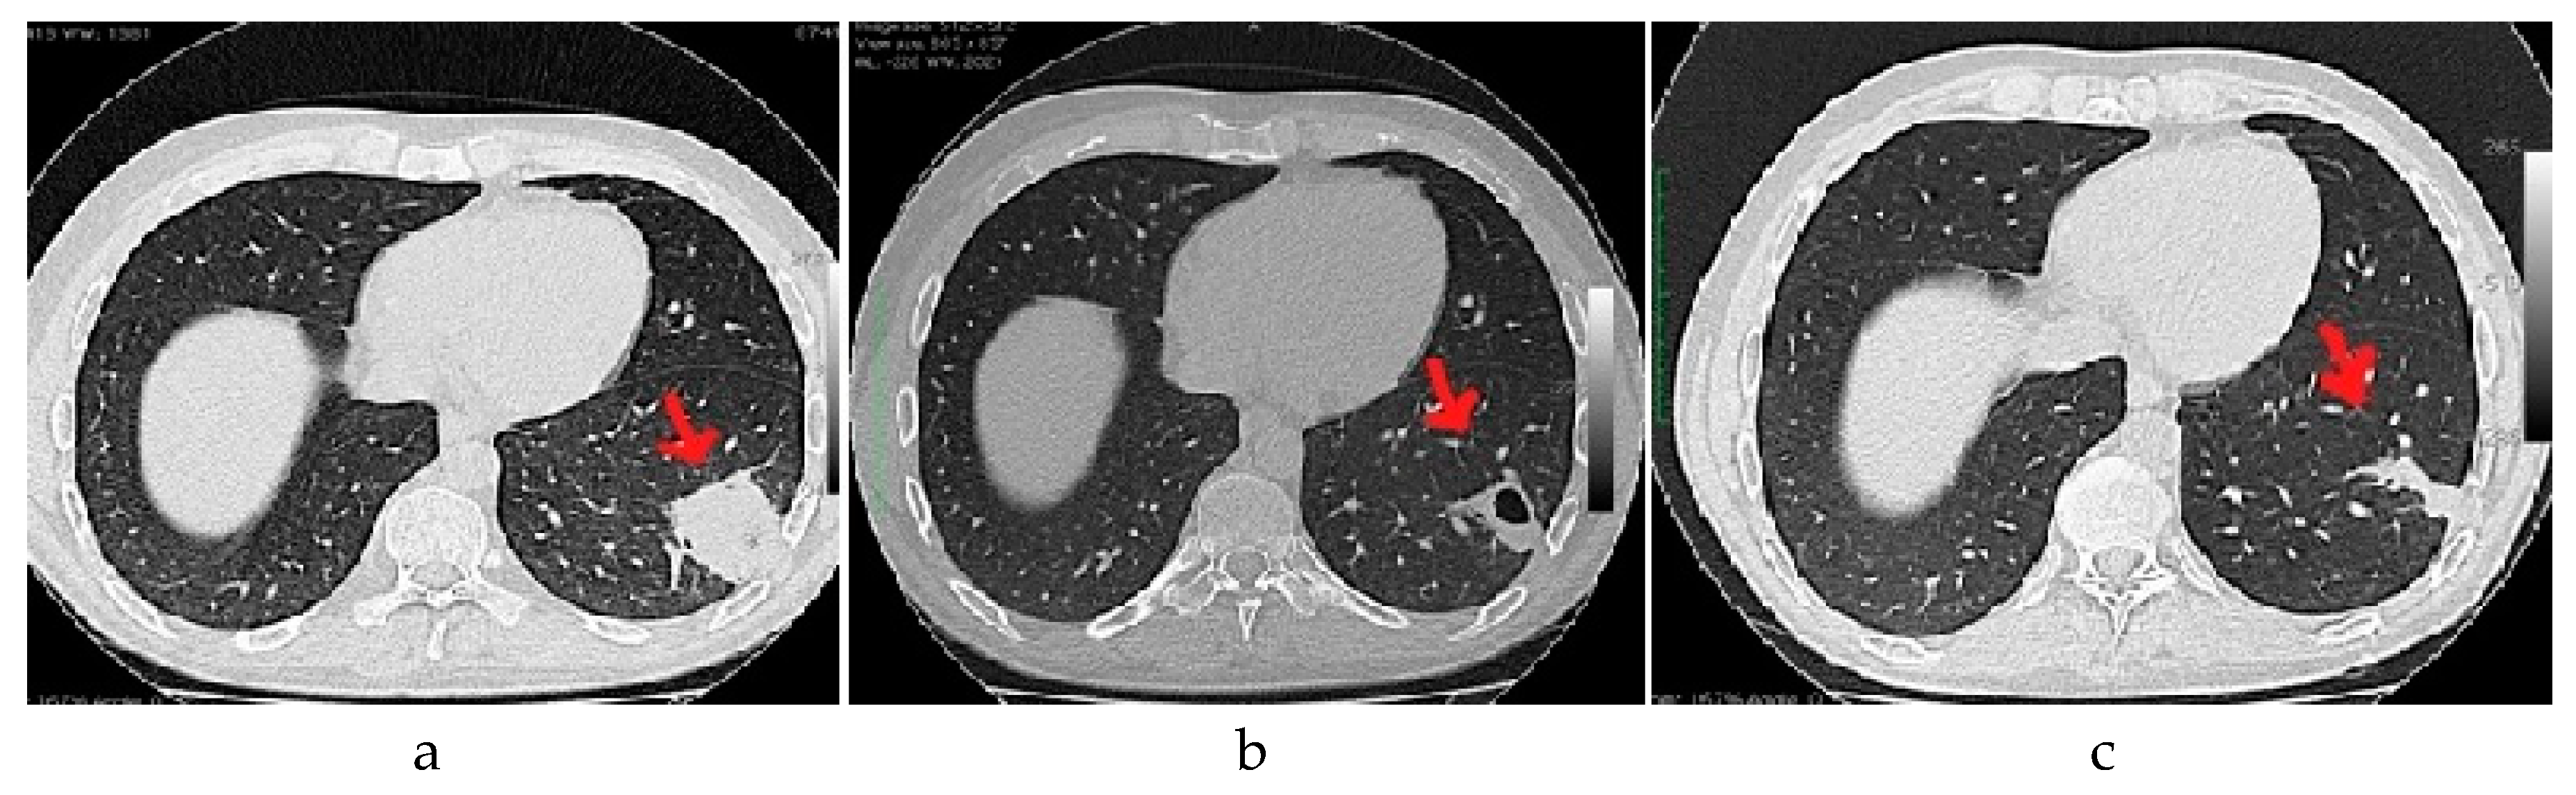

| Positive Chest CT Scan, n (%) | 10/23 (43.5%) |